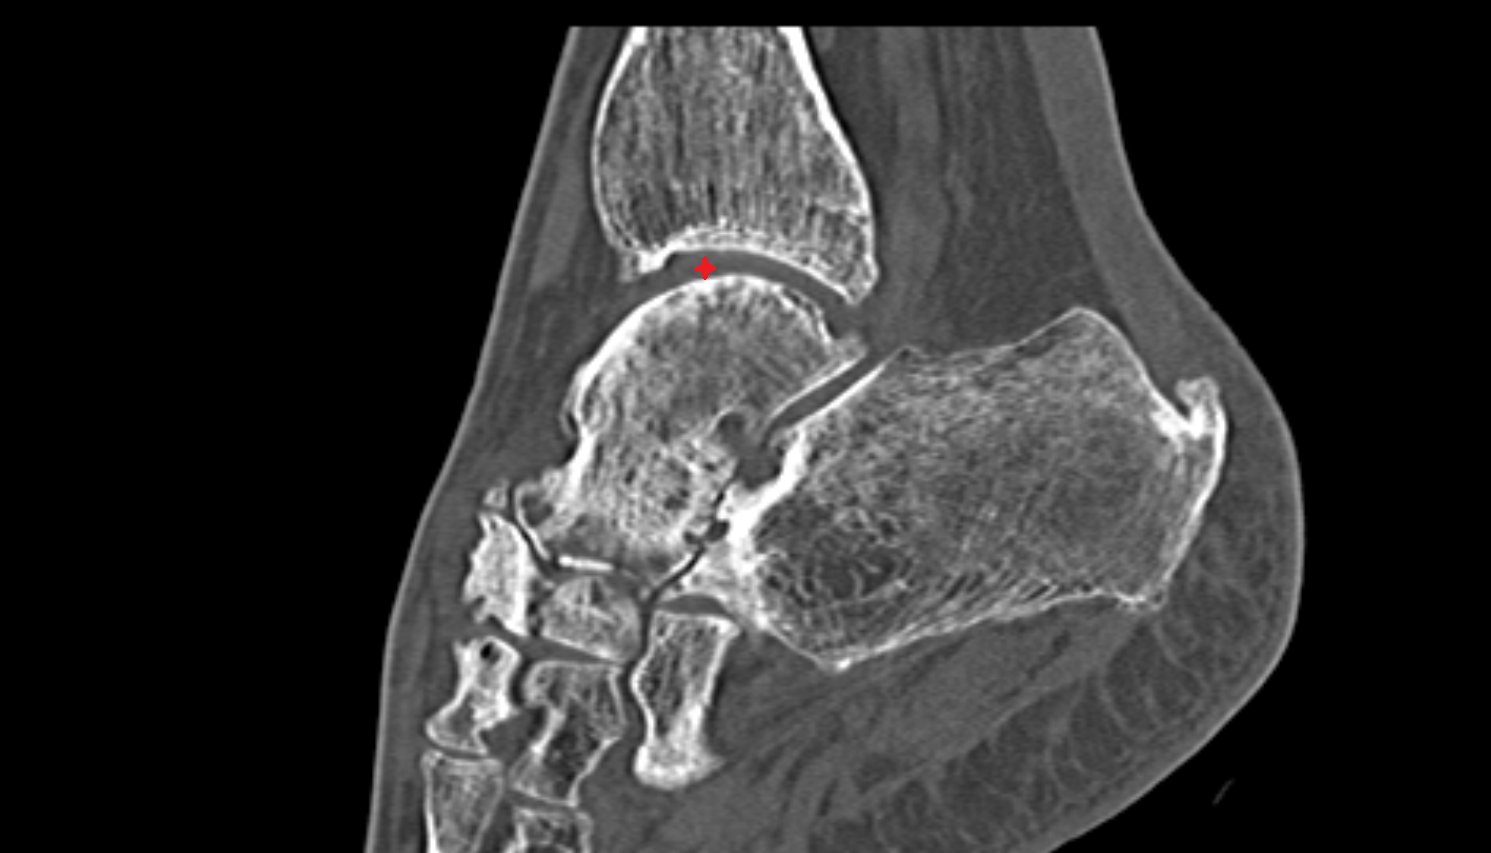

- Talus

- Body of talus

- Calcaneus

- Sustentaculum tali

- Ankle joint

- Talocalcaneal joint